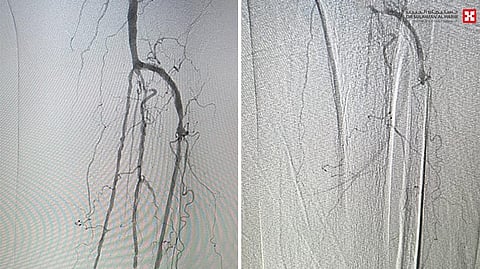

حيث تم استقبال المراجعة في عيادة الأوعية الدموية بالمستشفى، وتم إجراء الفحوصات السريرية والشعاعية اللازمة، وذلك لتقييم حالة الشرايين لديها مع مراجعة تاريخها المرضى. وبناءً على نتائج التقييم، وُضعت خطة علاجية متكاملة ، تضمنت إجراء قسطرة توسيعية دقيقة لشرايين الساق والقدم.

أوضح ذلك د. هيثم البشري والذي قال أن المراجعة خضعت لجراحة استغرقت ساعة ونصف ، باستخدام أحدث الأجهزة والتقنيات التداخلية المتقدمة لإعادة التروية الدموية إلى القدم، مما ساهم بشكل مباشر في تجنّب البتر للقدم واستعادة تدفق الدم بشكل فعّال. وقد غادرت المستشفى في اليوم التالي من العملية وهي بحالة مستقرة.